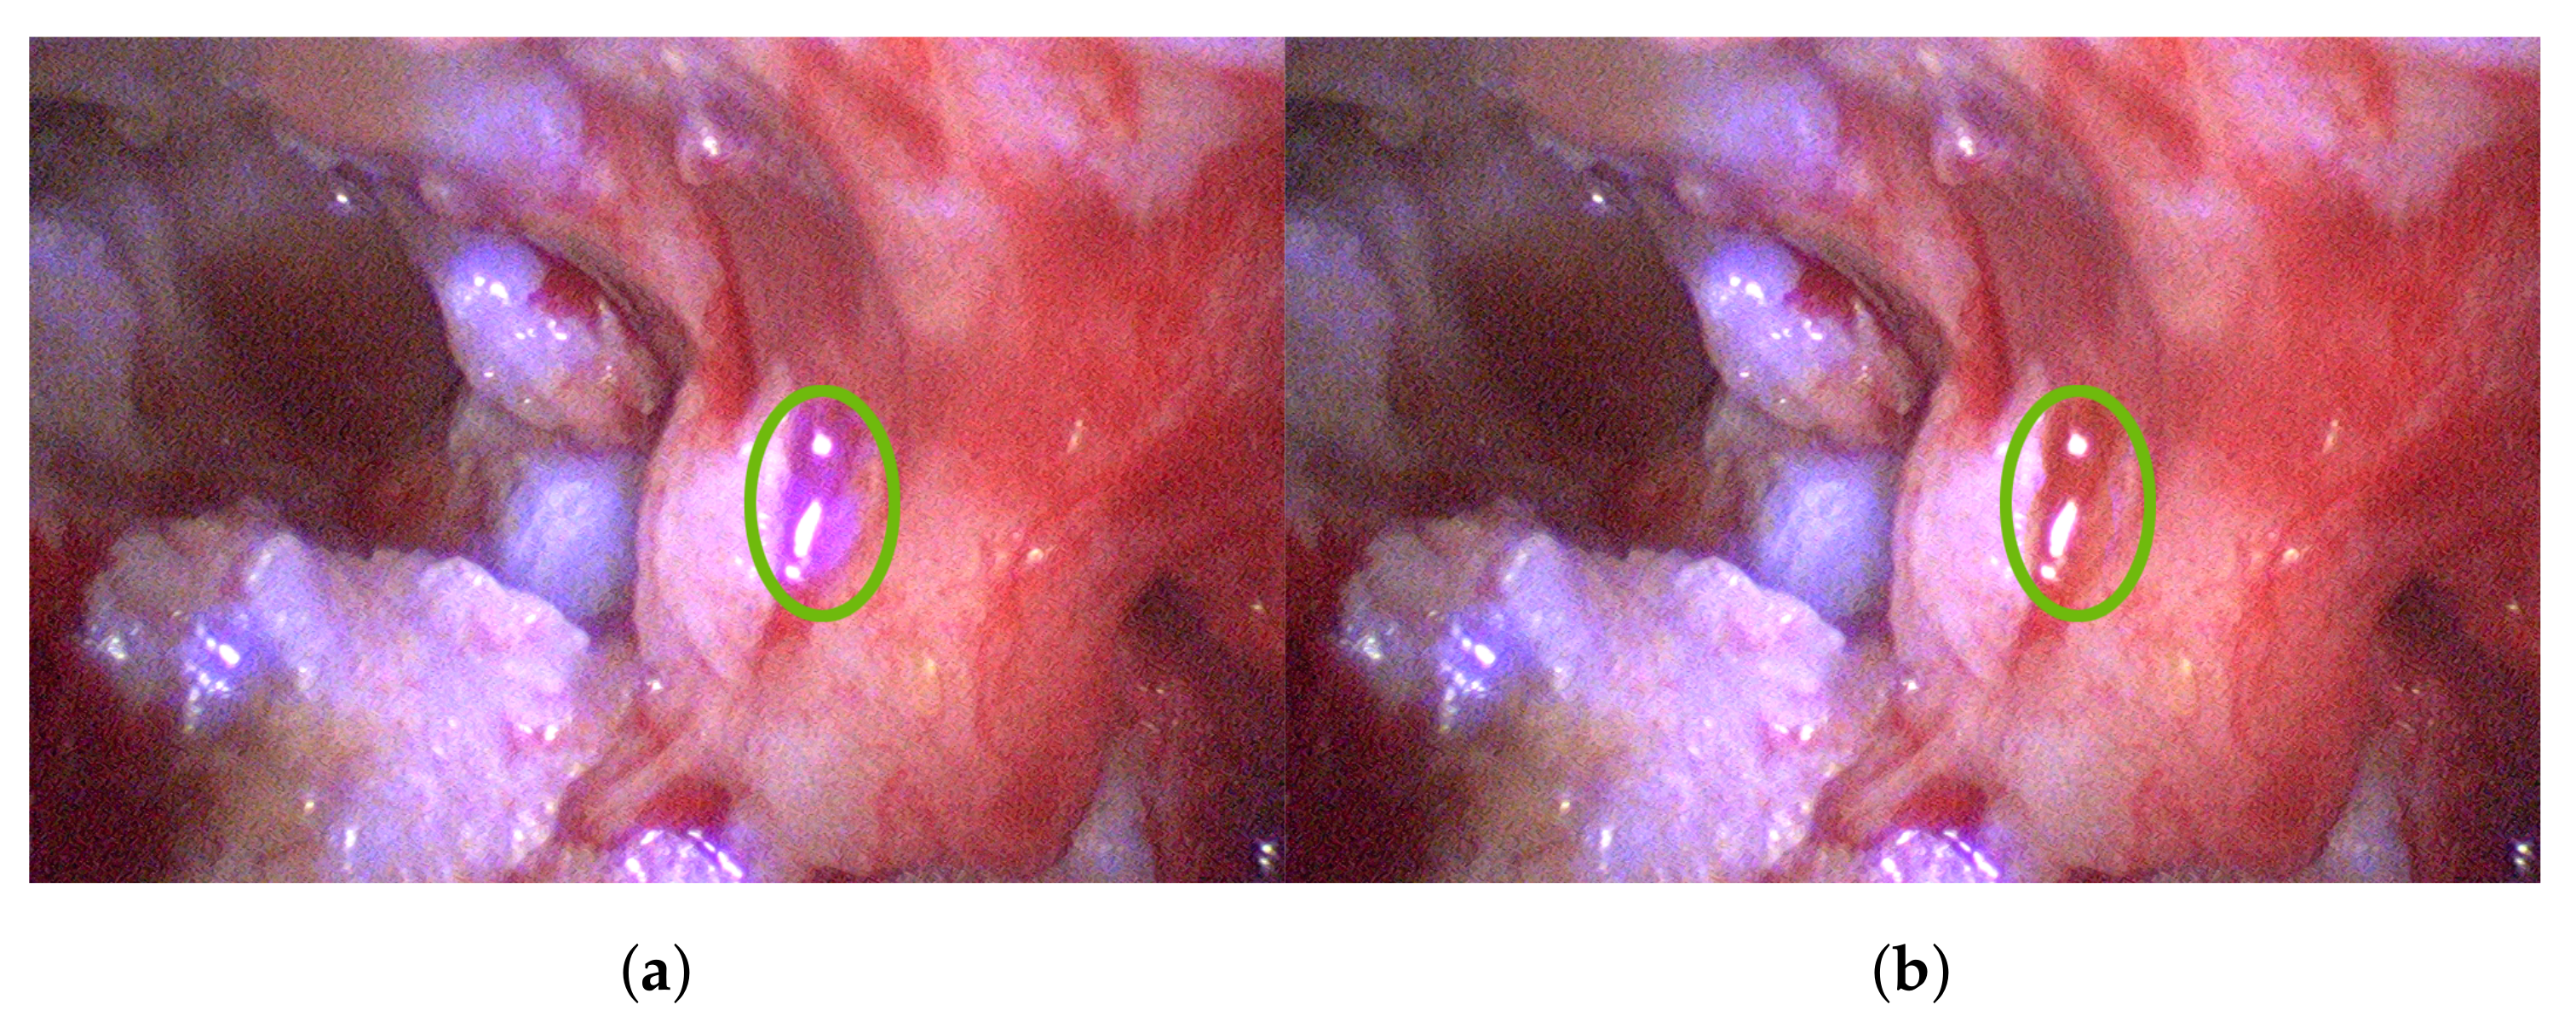

3.2. Cholesteatoma Visualization

3.3. Multispectral Stereo Acquisition